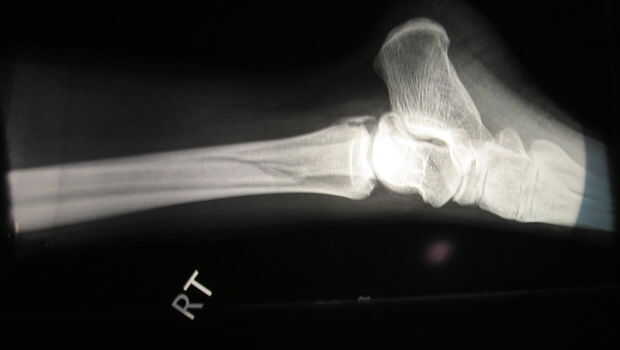

Tomó mucho tiempo para paramédicos demostrar para arriba. Eran ásperos y deseábamos que nos habíamos mudado su nosotros mismos. Aquí le damos la pierna después de que los paramédicos crueles arrancó lo nuevo de en forma de pierna.

historia más largo, ella pasó varios días con un tratamiento roto pierna, consiguió una placa de metal y un montón de tornillos para madera instalado, perdido su viaje de trabajo a Indonesia, etc. etc..